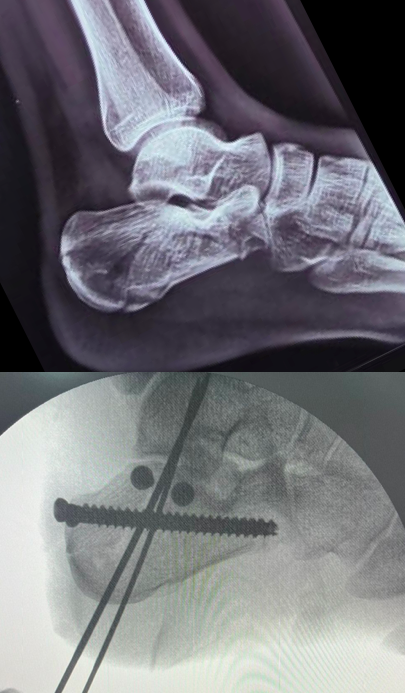

What’s your unpopular medical opinion that would land you in this position? Drop it in this thread